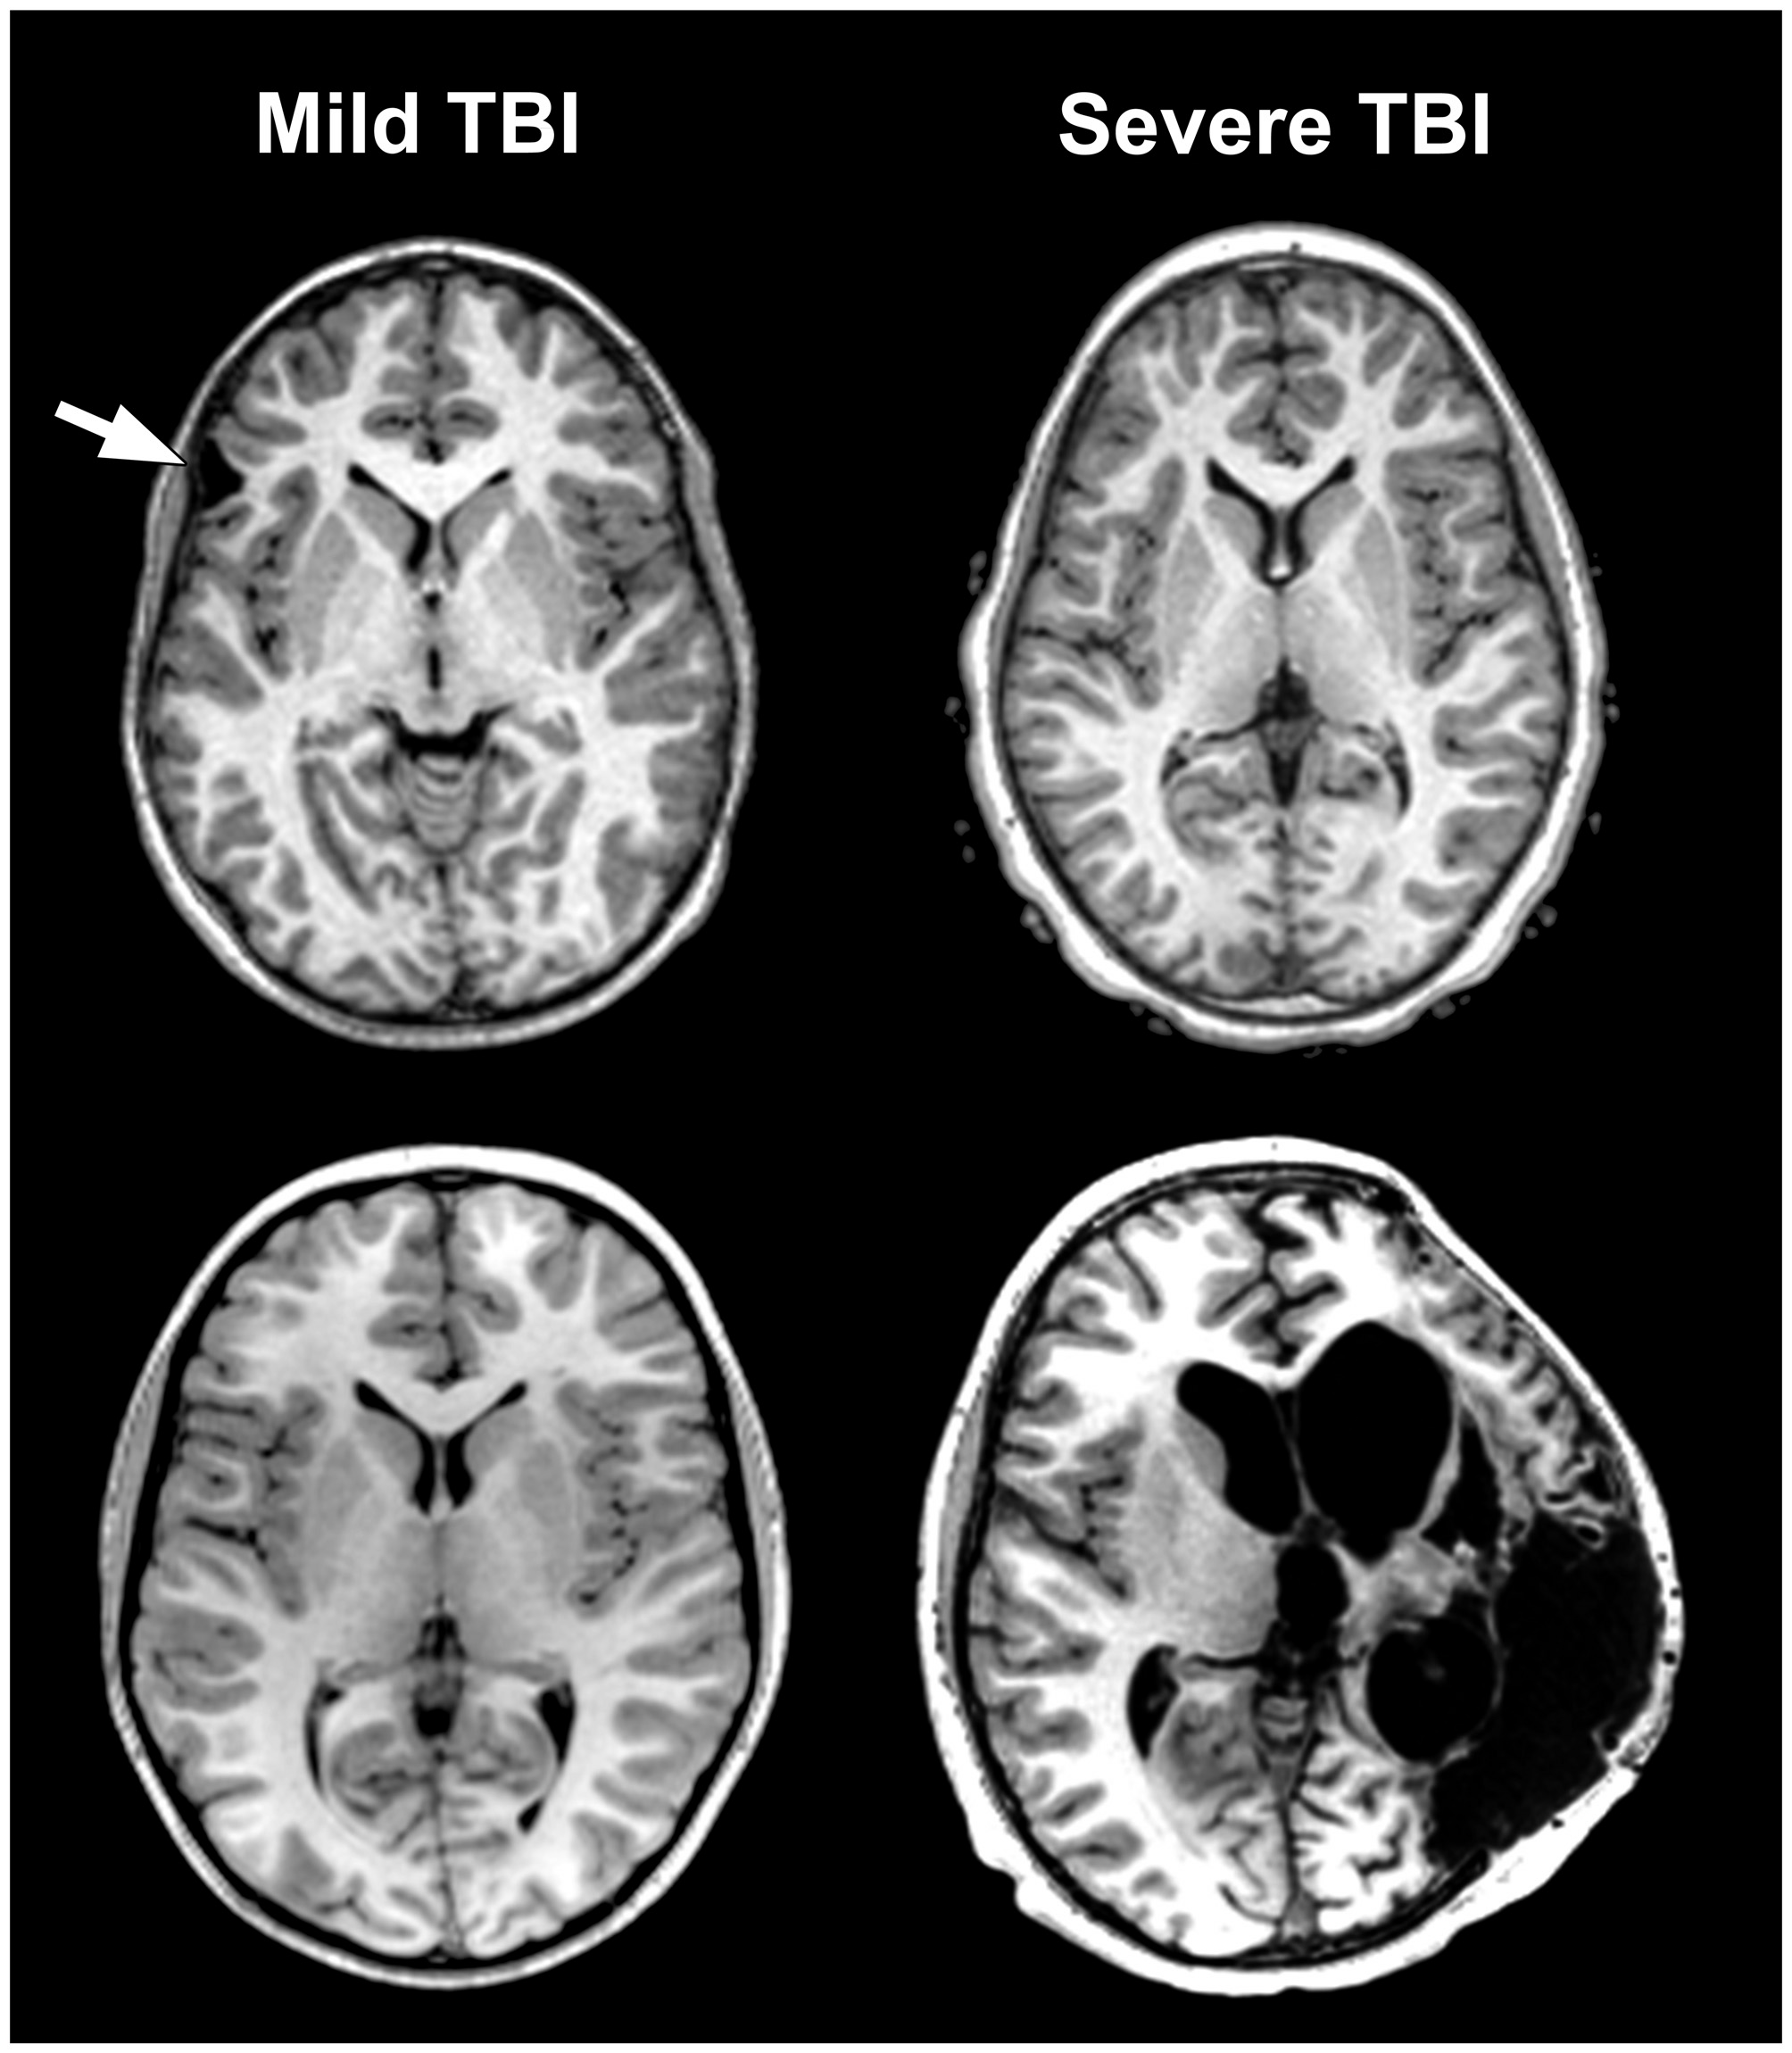

The International and Interagency Initiative toward Common Data Elements (CDE) for Research on Traumatic Brain Injury (TBI) and Psychological Health (see Menon et al., 2010) defines TBI as “… as an alteration in brain function, or other evidence of brain pathology, caused by an external force (p. 1637)” where severity is most commonly characterized by whether there was loss of consciousness (LOC) including its duration, post-traumatic amnesia (PTA) and/or Glasgow Coma Scale (GCS) ratings. While these features of TBI are important descriptors of the injury they provide only limited information about underlying neuropathology, or how the injury may relate to outcome but often, are the only uniform descriptors of a brain injury used clinically or in research, especially in neuropsychological outcome studies. The problem with this approach is immediately grasped by viewing Figure 1. Patients with identical GCS scores, or whether LOC occurred or not, may have similar or widely diverse neuropathological findings on magnetic resonance imaging (MRI) at the same chronic stage post-injury. If a neuropsychological outcome study were to use only GCS, PTA, LOC or some similar injury severity rating, cases like in Figure 1 become lumped together with incredibly diverse underlying neuropathology. This diversity of pathology also means that any singular neuroimaging metric used to assess pathology will underestimate the totality of pathological effects or fail to even detect presence of a pathological change in the brain brought on by the trauma.

Figure 1. The problem of traumatic brain injury (TBI) severity classification by using the Glasgow Coma Scale (GCS) is the wide disparity of structural pathology that may be present for a given classification level. Traditionally, mild TBI (mTBI) has been classified by GCS scores between 13–15. The arrow in the case presented in the upper left depicts a prominent focal area of frontal encephalomalacia as a residual from an old contusion in this individual who had a mTBI and an initial GCS = 14. Note that the asymmetry of the anterior horn of the lateral ventricular system on the side of the lesion that is likely a subtle reflection of greater parenchymal volume loss surrounding the side of the lesion. In contrast, the case in the lower left or the one in the upper right have no visible abnormality, despite GCS scores of 15 and 3, respectively. Finally, the obvious massive structural damage in the lower right is from a TBI patient with severe TBI and GCS of 3. The case in the upper left had a reported brief loss of consciousness (LOC) but the other individual with mTBI (lower left) did not. Both severe TBI cases also had positive LOC.

The basis for much of the confusion generated in the neuropsychological literature about TBI outcome is likely the result of combining cases with differing TBI-related pathology examined only with basic neuroimaging metrics. For example, in Figure 1 the axial images from a MR scan of two individuals who sustained severe TBI are shown on the right side of the figure. One demonstrates no observable gross pathology while profound abnormalities are distinctly visible in the other. In the child with extensive structural pathology there is parenchymal loss, shape distortion and multiple variations in MR signal intensity that deviate from the norm, each indicating differences in the types of neuropathological changes that have occurred. For the two cases with mild TBI (mTBI) shown on the left of the figure, one had a sizeable frontal lesion, the other no abnormality, just like one of the severe TBI cases (upper right). Also evident from viewing Figure 1 is that there is a tremendous amount of information in those images about the size, volume, shape, length, thickness, etc., of brain structures, as well as visible pathology when present, all of which can be quantified. Improved identification and quantification of brain images, including a multi-modality approach to comprehensively identify abnormalities should improve the predictive ability of neuropsychological outcome studies and likewise better inform treatment and follow-up for the TBI patient. However, what neuroimaging measures to use and within what framework TBI neuropathology is identified represent complex, unresolved issues and the basis for this review.

Masel and DeWitt (2010) argue that TBI should not be viewed as an event, but as a disease process (see also, Masel, 2015). This makes sense because even though TBI clearly has an exogenously defined onset, as stated in the definition above, the injury sets into motion a cascade of various pathological effects (Johnson et al., 2013, 2015; Smith et al., 2013; Armstrong et al., 2015, 2016; Mierzwa et al., 2015), some of which may be purely short-lived and transient, while others are chronic. Chronic effects from TBI are sufficiently common and disabling that TBI meets criteria as a disorder with a major world-wide disease burden (Olesen and Leonardi, 2003). Since there is a time-dependent staging to injury effects, neuroimaging analyses need to be dynamic (Kim and Gean, 2011). If there are a multitude of pathological factors initiated by the injury, then characterizing them by various features extracted from neuroimaging variables should not be singular but as comprehensive and thorough as possible. As pointed out in Figure 1, it is a mistake to just characterize TBI by one of the markers of injury severity. It would be equally a mistake to characterize the neuroimaging identified neuropathology by a single measure (i.e., presence/absence of a focal lesion). But how should neuroimaging findings be analyzed, within what theoretical framework and how should these metrics be applied to outcome research and clinical use? What are some of the best ways to conceptualize traumatically induced neuropathology using current neuroimaging technology? These are the issues of this review.

Returning to Figure 1 the abnormalities that are highlighted reflect differences between each patient and likely relate to different aspects of TBI pathology. Given this striking heterogeneity, it immediately becomes apparent that there is no universally occurring “lesion” in TBI. It would also be unsatisfactory to approach this within a simple framework of the size or just where a definable abnormality may be located, which up to this time has been a common approach to neuropsychological outcome studies. Additionally, as will be explained more fully below, the information contained within a MR scan is unique to that individual, but most TBI studies approach neuroimaging analyses via group data comparisons. Whatever neuroimaging analysis tools emerge, they must be able to account for individual differences in brain structure and function but also appropriately identify all types of pathology potentially discernable from an image.